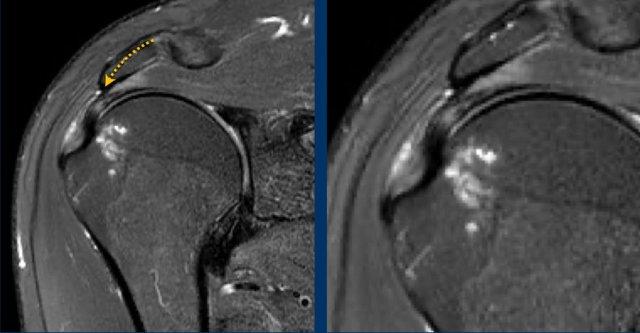

Hình ảnh

Trên chuỗi xung T2W có một tổn thương rách mặt túi hoạt dịch kích thước lớn.

Lưu ý rằng trên MRI khớp có thuốc tương phản từ, tổn thương rách không quan sát thấy do thuốc tương phản từ nội khớp không thể tiếp cận vị trí khuyết trong gân.